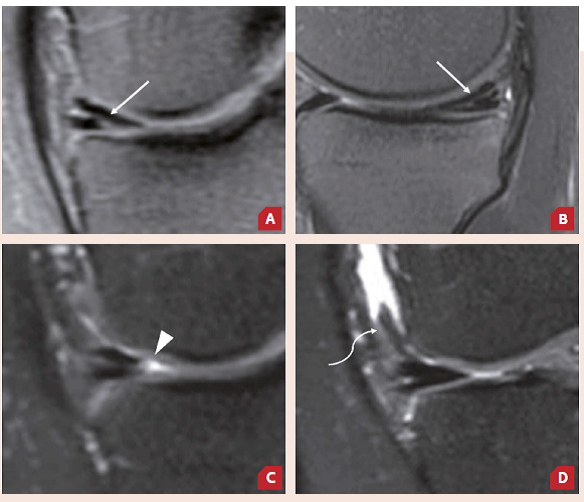

Paciente de 29 anos, sexo feminino, RM pré e pós-operatória de lesão em “alça de balde” do menisco medial. Atualmente assintomática.

A e B) Exames pré-operatórios. A) Sequência coronal DP FS exibe a rotura em “alça de balde”, com redução volumétrica e irregularidade dos contornos do corpo do menisco medial e fragmento meniscal (cabeça de seta) deslocado para a região intercondilar. B) Sequência sagital T2 FS evidencia extensão de rotura horizontal ao corno posterior do menisco (seta). C e D) Exames de controle após um ano do pós-operatório, com boa evolução clínica. C) Sequência coronal DP FS mostra a restauração da morfologia habitual do corpo do menisco medial, sem mais fragmentos meniscais deslocados, com persistência de alteração de sinal na topografia do reparo, relacionada a tecido de granulação/cicatricial. D) Sequência sagital T2 FS traz o sítio de reparo do corno posterior, também com persistência de alteração de sinal intermediário, relacionada à cicatrização meniscal. Tais achados indicam sinais de boa evolução do reparo.